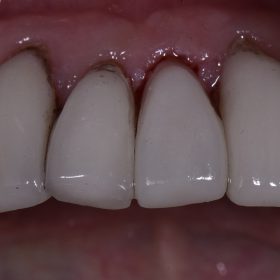

Porcelain Veneers | Cosmetic Dentistry Auckland

Porcelain veneers can cover a multitude of sins. Using a thin shell of handcrafted ceramic, dark and yellow teeth can be made to look virginal and white again. Porcelain is […]